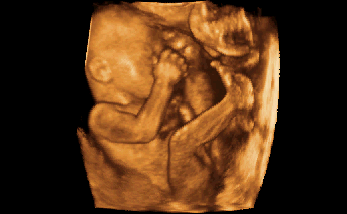

3-D / 4-D Ultraschall

Beeindruckend ist die dreidimensionale Darstellung in der Schwangerschaft, besonders wenn die Bewegungen des Babys zusätzlich "live" gesehen werden können (4-D). Dies gibt Ihnen als werdende Mutter einen ersten Blick auf ihr Kind und damit Sicherheit und Beruhigung.

Nebenan sehen Sie Beispiele für die dreidimensionale Darstellung